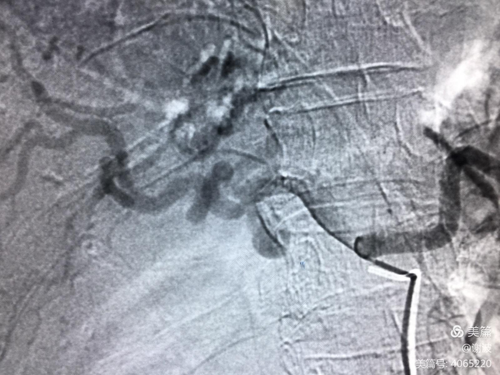

在积极治疗的同时需要做手术前的准备,然后联系手术室,尽早进入手术室,进行剖腹探查手术,在手术中应当要找到出血的位置,然后结扎住血管,控制出血,如果是由于肿瘤而引起的,必要时可以做二次手术治疗。